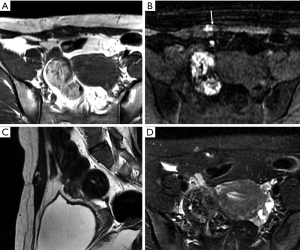

On CT and MRI, ALTs/WDLs typically have a relatively characteristic appearance of predominantly adipose masses containing nonlipomatous components (14-20). Distinguishing ALTs/WDLs from benign lipoma can be challenging and often requires histological evaluation. Imaging features suggesting an ALT/WDL or liposarcoma include tumor heterogeneity, thickened or irregular nodular septa (generally more than 2-mm thick), nodular soft tissue or nonadipose components, and incomplete fat suppression with linear or nodular hyperintense areas on MRI (9,12,19-22) (Figure 2).

Liposarcomas

Liposarcomas are the second most common soft tissue sarcomas, accounting for 10–35% of all soft tissue sarcomas (13). Liposarcomas show the most striking diversity in pathological and biological behavior and can be categorized into several subtypes, including dedifferentiated, myxoid, pleomorphic, and mixed (23). The imaging findings of liposarcomas are frequently distinct. On CT and MRI, focal or diffuse areas of fat associated with nonlipomatous components are commonly detected, and the diagnosis can be easily determined in these cases. However, the diagnosis is not achievable in other cases without fatty tissue in the lesions (Figure 3). MRI is useful for distinguishing well-differentiated from poorly differentiated liposarcomas (11).